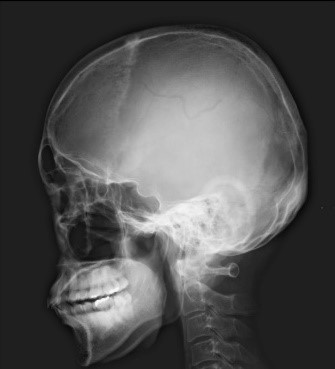

Загальна рентгенографія

Педіатрія